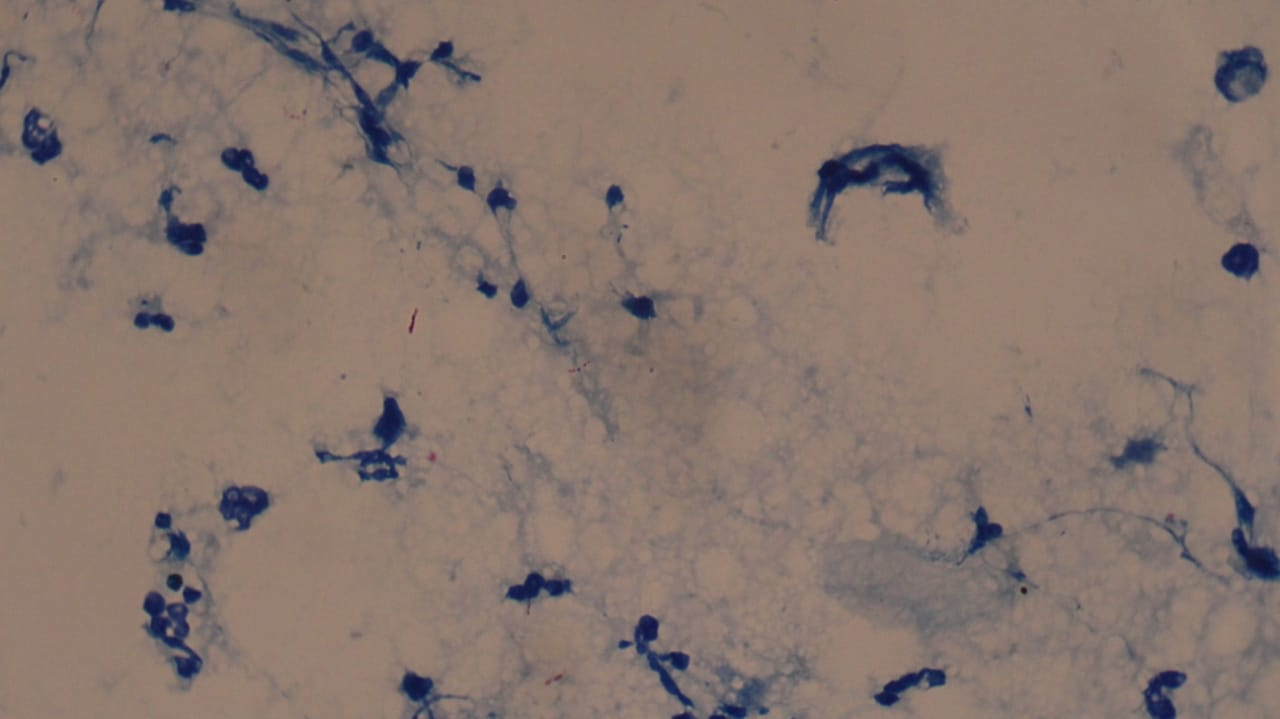

A diagnosis of bronchopneumonia was made. The distress was not improving with oxygen through nasal prongs, so the child was connected to hot humidified high flow nasal canula (HHHFNC). Chest X ray revealed non-homogenous opacity bilaterally (Figure 1) and hence IV broad spectrum antibiotics were given for 10 days. As the distress settled, HHHFNC was tapered, stopped and shifted to ward. The child developed high grade fever and worsening of symptoms with increased work of breathing in another 2 days, hence oxygen was restarted.

Figure 1 Chest X ray of the patient at admission, showing non homogenous opacity bilaterally more on right side.